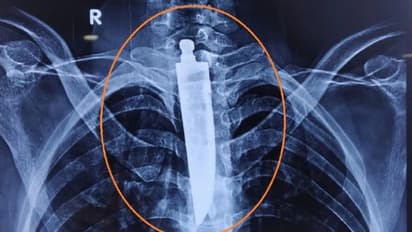

भोपाल (मध्य प्रदेश). कभी-कभी इंसान का आश्चर्यजनक चीजें मुंह में डालने का शौक बहुत भारी पड़ सकता है। इतना नहीं कई बार तो उसकी जान पर भी बन आती है। ऐसा ही एक हैरान करने वाला मामला भोपाल के अखिल भारतीय आयुर्विज्ञान संस्थान एम्स से सामने आया है। जहां एक 32 साल के युवक की सर्जरी कर उसके फेफड़े में फंसे 14 सेंटीमीटर (करीब 6 इंच) लंबे चाकू को किसी तरह निकाला गया है। आश्चर्य की बात यह है कि युवक ने चाकू से पेन की रिफिल भी निगल ली थी।

दरअसल, चाकू निगलने वाला यह शख्स छतरपुर का रहने वाला है। डॉक्टरों ने बताया कि युवक इससे पहले भी कई बार लोहे की वस्तुओं को निगल चुका है। दो साल पहले जिला अस्पताल में ऑपरेशन कर उसके पेट से कई अजीब चीजें निकाली जा चुकी हैं। (फोटो आजतक)

युवक के परिजनों ने बताया कि युवक को पिछले कुछ दिन से निगलने में परेशानी हो रही थी। इसके अलावा उसके गले में दर्द भी बना रहता था। जब उसकी ईएनटी विभाग के सर्जन डॉक्टरों ने उसकी गर्दन का एक्स-रे किया, तो वह यह देखकर हैरान रह गए। क्योंकि उसके फेंफड़ों में कुछ रॉड नुमा दिखाई दे रहा था। जब एंडोस्कोपी की गई तो पता चला कि चाकू फंसा हुआ है।

भोपाल एम्स के डॉक्टरों ने मामले को गंभीरता से लेते हुए युवक की फौरन सर्जरी करने का फैसला किया। भोपाल एम्स के निदेशक डॉ रमन सिंह ने मीडिया को बताया कि यह ऑपरेशन बहुत कठिन था, इसमें युवक की जान भी जा सकती थी। क्योंकि चाकू की लंबाई 14 सेंटीमीटर थी। जिससे एलिमेंटरी कैनाल के अलावा, यह मस्तिष्क को रक्त पहुंचाने वाली नसों को भी नुकसान पहुंचा सकता है।

एम्स के डॉक्टरों ने बताया कि चाकू ना अगला हिस्सा युवक के दिल की मुख्य धमनी तक पहुंच गया था। इसी बीच उसकी सर्जरी करना था। ऐसे में हमारी स्पेशल सर्जन टीम को इस ऑपरेशन करने में  4 से 5 घंटे का समय लगा।  अब युवक पूर्ण रुप से ठीक है।